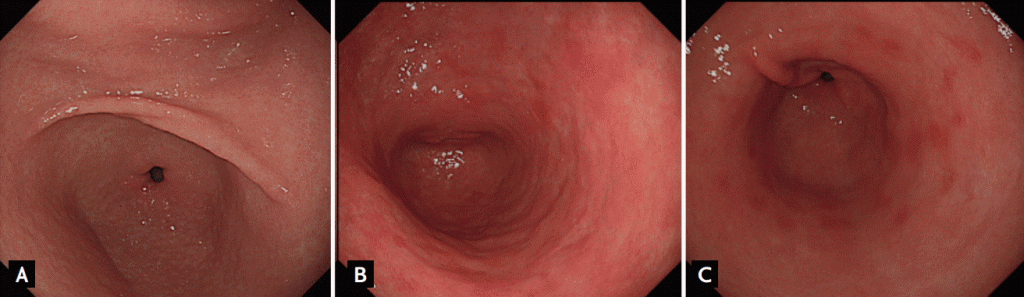

Endoscopic findings of CAG and MG

Endoscopic changes due to gastric atrophy are consequences of long-term H. pylori infection which progress from lesser curvature side of the antrum to greater curvature side of the corpus. Endoscopic findings of CAG reveal the extent of gastric atrophy by showing an atrophic border consisting of visible transparent vessels (Fig. 4). Endoscopy is a reliable method with high reproducibility which was shown to predict histological atrophy in a multinational study. Gastritis staging, so-called operative link on gastritis assessment (OLGA) staging, provides information on the gastric mucosa by integrating the atrophy score and topography. More recently, the Kyoto Global Consensus Meeting developed a global consensus on the classification of chronic gastritis. It is important to discriminate endoscopic findings based on their characteristics (Fig. 5).

In countries where H. pylori infection-related chronic gastritis is common, endoscopic findings or the serum PG assay are often combined to evaluate CAG and MG. MG exhibits various endoscopic findings such as irregular whitish mucosa, a villous appearance, mucosa with an uneven-surface, and patchy redness. Notably, CAG and/or MG induce spontaneous regression of H. pylori, because it is difficult for the bacterium to survive in the hypoacidic environment produced by severe CAG and/or MG. Greater curvature side of the upper corpus seems to be the least atrophic and metaplastic site, and is the location in which H. pylori can survive for the longest period of time before spontaneous regression.